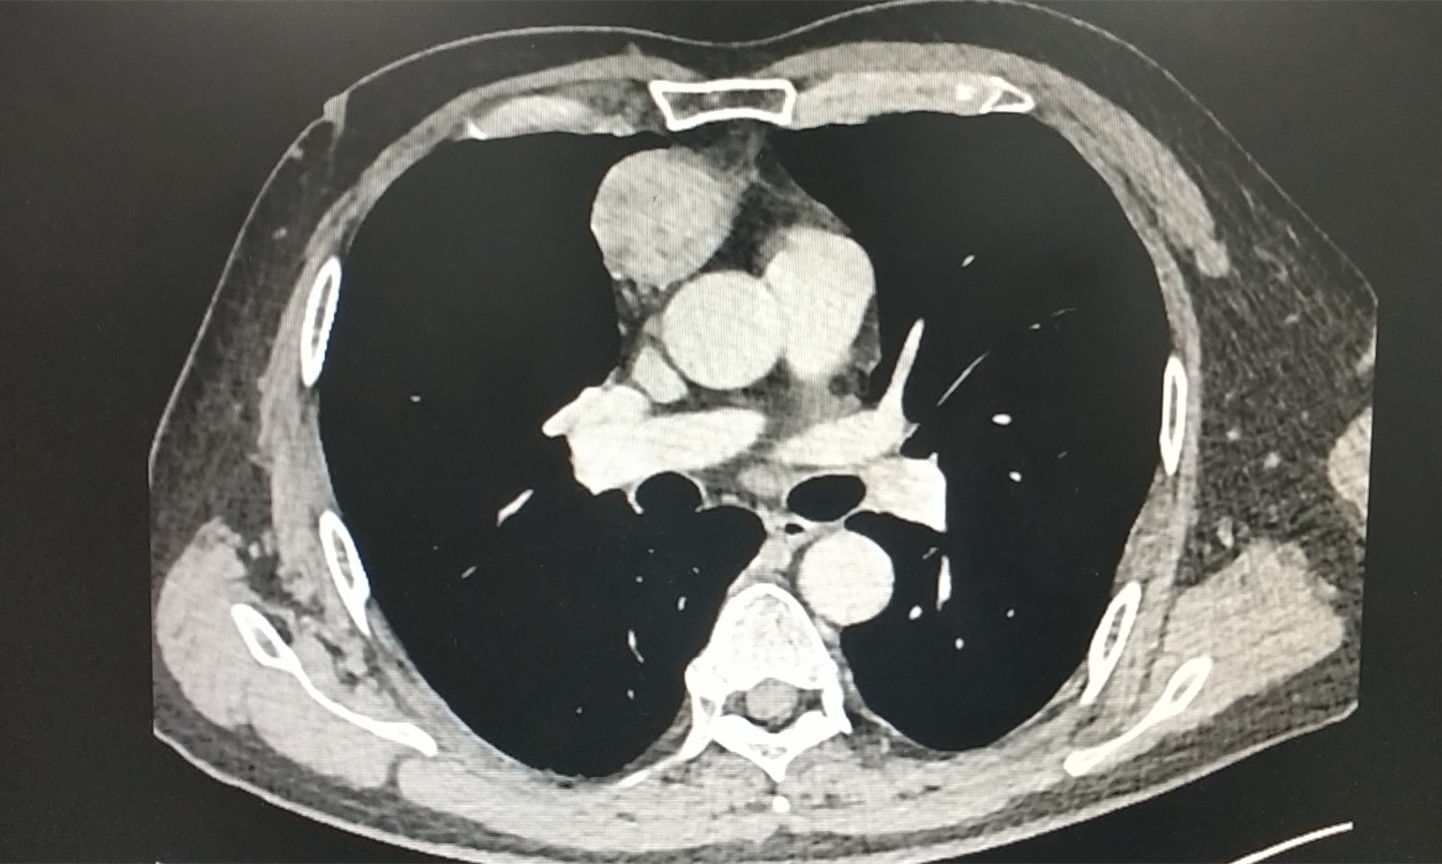

文章插图

患者胸腺病变在CT下的成像情况